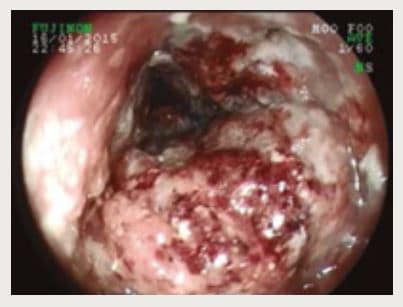

Se le realizo una endoscopía digestiva alta (Figura 2) donde se evidencia distensibilidad esofágica muy disminuida corroborándose los hallazgos previamente descritos y se realiza una biopsia.

Figura 2. Extensa lesión proliferativa, de color violáceo por sectores, con gran friabilidad al roce, abundante cantidad de fibrina y zonas de necrosis.